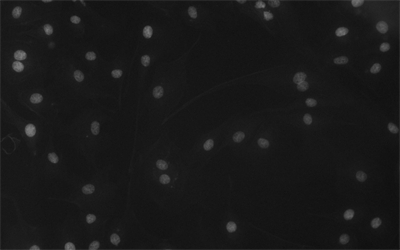

MHS700-MC(黑白)相機(jī)采用Sony Exmor CMOS芯片,針對傳感器固有的熱噪聲,專門設(shè)計了高效制冷模塊使得相機(jī)傳感器的工作溫度比環(huán)境溫度低達(dá)-40度,大大降低了圖像噪聲,保證了圖像質(zhì)量的獲取。

分辨率橫跨710萬,實時8/12位切換,任意ROI尺寸,Ultra-FineTM顏色引擎確保顏色精準(zhǔn)再現(xiàn),快速地完成對相機(jī)的各種設(shè)置,曝光超速抓拍,實現(xiàn)完美顏色再現(xiàn)能力。

相機(jī)可用于弱光或熒光圖像的拍攝與分析,主要應(yīng)用于以下領(lǐng)域顯微拍攝:

• 活體細(xì)胞成像,細(xì)胞或組織病理學(xué)檢測,細(xì)胞學(xué);

• 微光熒光成像,GFP 或 RFP 分析,熒光原位雜交(FISH);